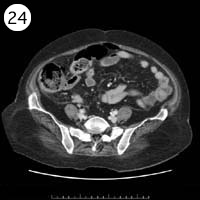

57歳 女性

単純CT

造影CT